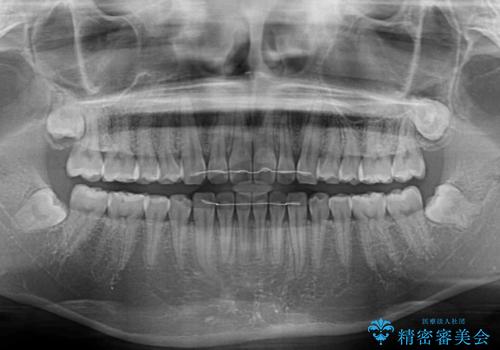

すきっ歯とオープンバイト インビザライン・ライトで改善

オープンバイトのため、奥歯に負担のかかる咬合状態であったので、矯正治療を提案したところ、希望をされました。

すきっ歯程度の軽度の歯列不正であったため、インビザライン・ライトにより咬合改善を行うこととしました。

オープンバイトやすきっ歯は、舌突出癖によりあっという間に後戻りをするため、矯正治療前からトレーニングを行っていただき、更には後戻り防止のワイヤーリテーナーを併用しています。